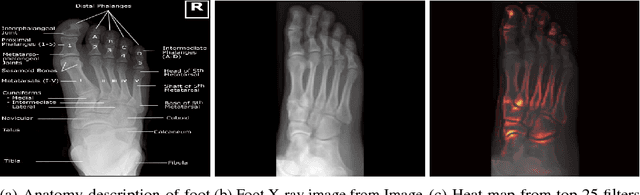

Abstract:One of the main challenges for broad adoption of deep learning based models such as convolutional neural networks (CNN), is the lack of understanding of their decisions. In many applications, a simpler, less capable model that can be easily understood is favorable to a black-box model that has superior performance. In this paper, we present an approach for designing CNNs based on visualization of the internal activations of the model. We visualize the model's response through attentive response maps obtained using a fractional stride convolution technique and compare the results with known imaging landmarks from the medical literature. We show that sufficiently deep and capable models can be successfully trained to use the same medical landmarks a human expert would use. Our approach allows for communicating the model decision process well, but also offers insight towards detecting biases.